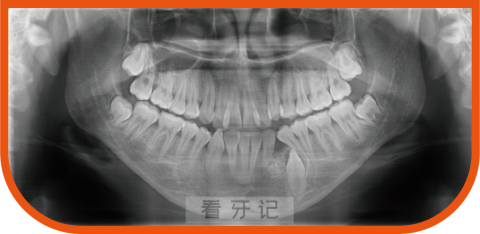

10. 埋伏牙:牙齿没有萌出,埋伏在颌骨里,可通过拍摄X线片诊断。